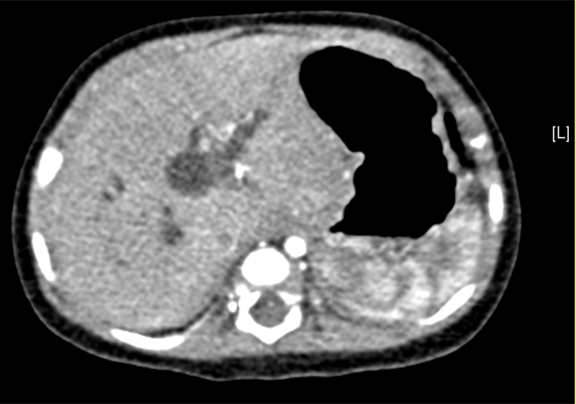

术前CT检查:

平衡期

上腹部增强CT:先天性胆管扩张症(胆总管囊肿)可能性大。

将0.625mm双源薄层CT资料的静脉期和动脉期Dicom格式文件导入海信CAS系统。

通过调节窗宽窗位调整CT序号,对肝实质,胆囊,下腔静脉,肿瘤,肝动脉、门静脉及肝静脉等进行三维重建;系统自动计算肝脏体积。